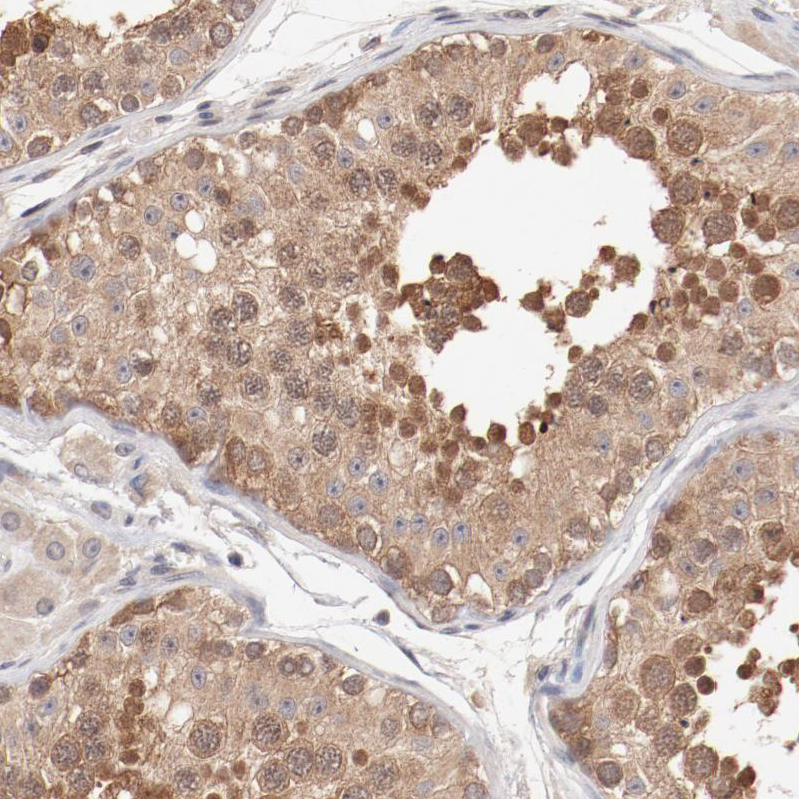

Immunohistochemical staining of human testis shows moderate cytoplasmic positivity in cells in seminiferous ducts.